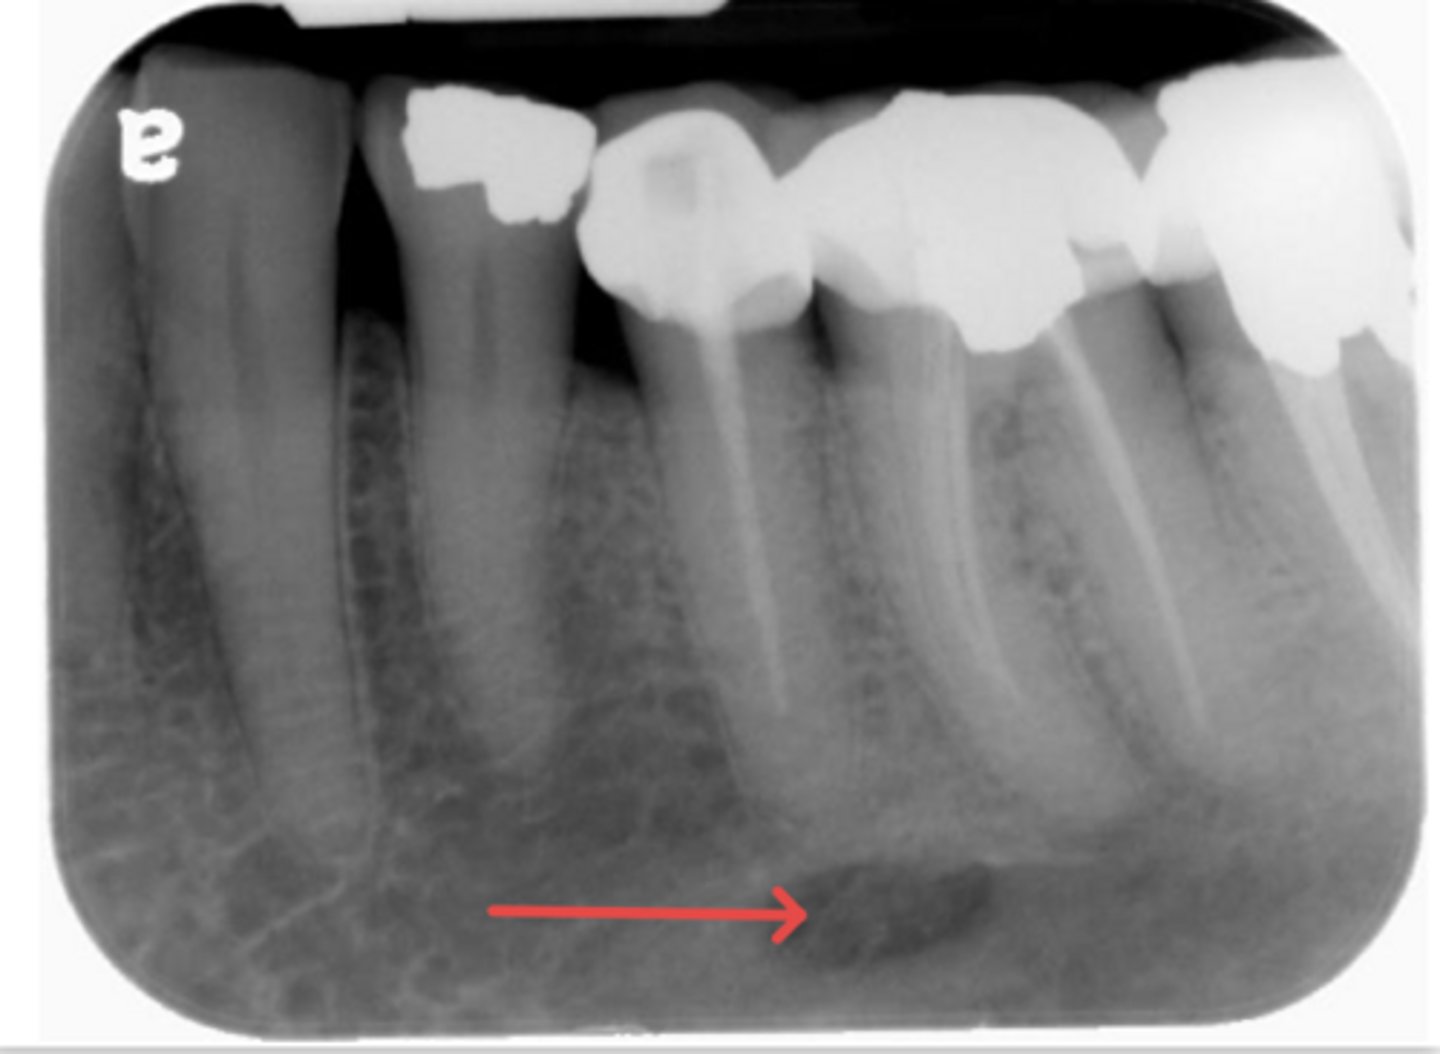

ID the structure:

submandibular gland fossa